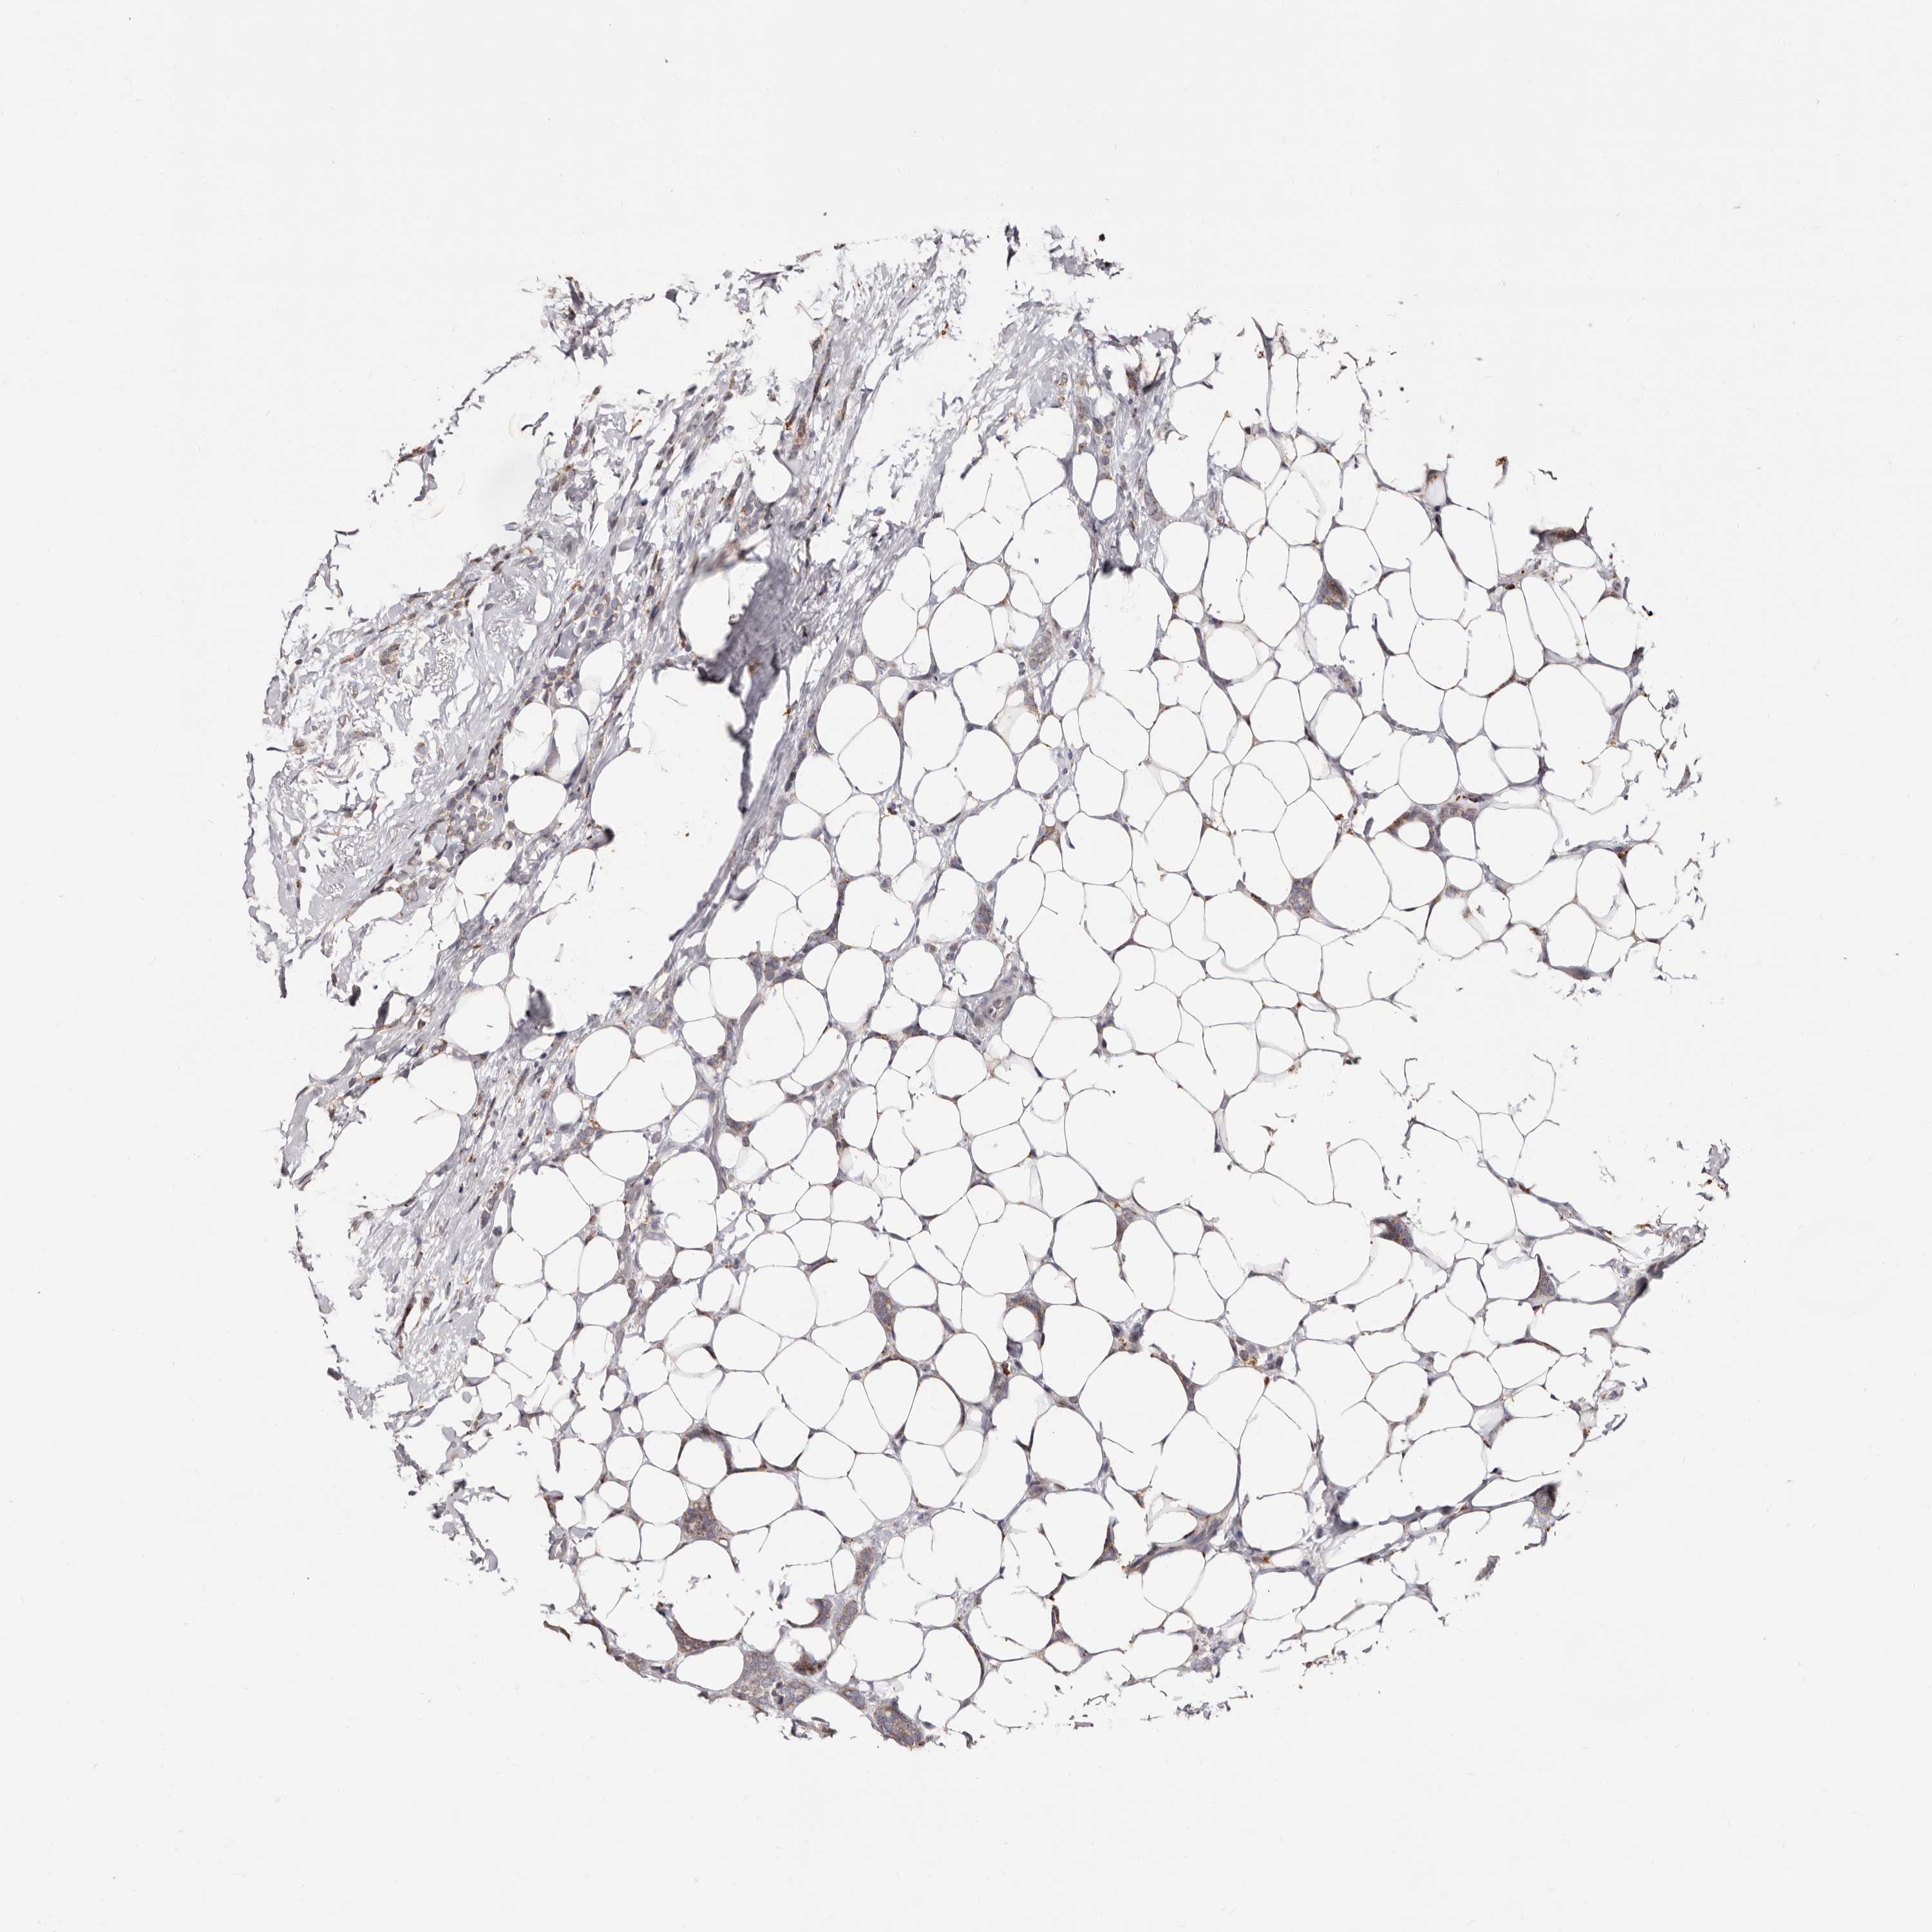

CANCER BREAST CANCER Show tissue menu

BRCA TCGA BRCA VALIDATION PROTEIN EXPRESSION